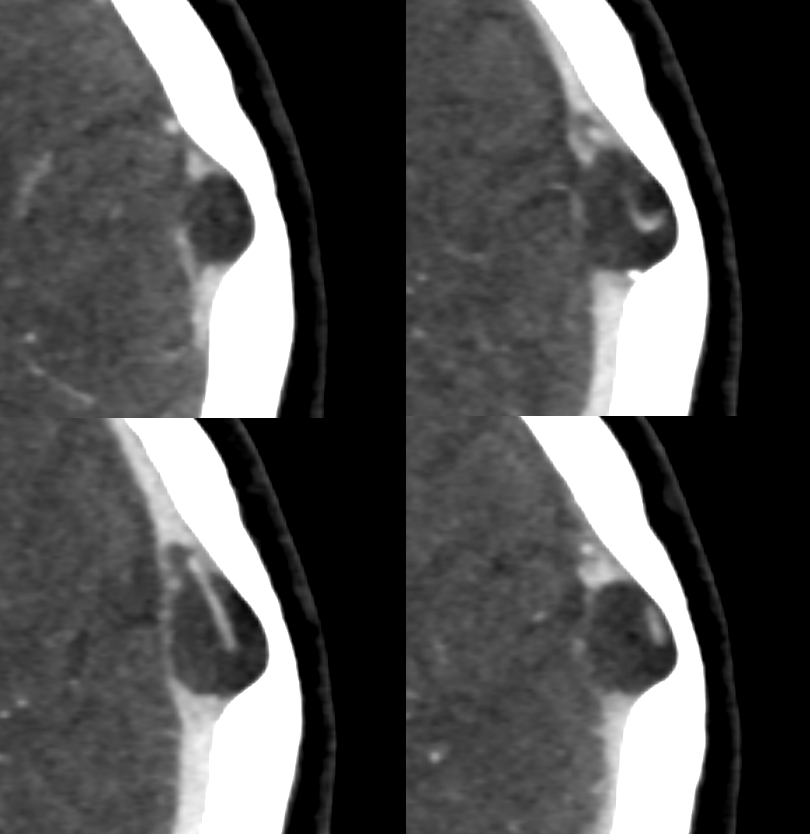

CISS Sequence — larger ones have veins inside them. Asymptomatic